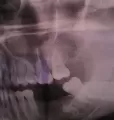

Здравствуйте! Есть ли у меня киста? Если да, то как срочно нужно делать операцию и как она называется?

Какой зуб вы имеете ввиду? Уточните. 18 и 48 зуб необходимо удалить. Далее расскажу после уточнения.